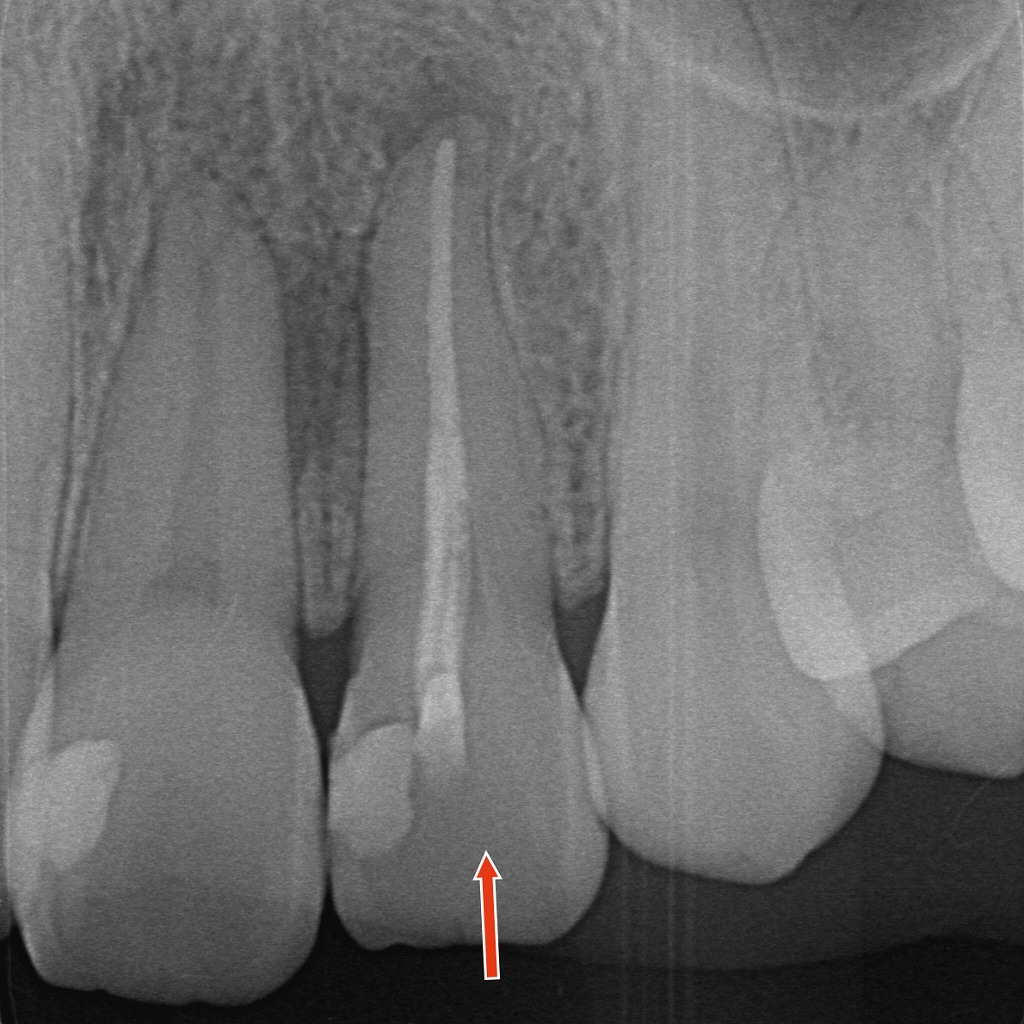

◆レントゲン画像(神経のない前歯の状態)

矢印の歯は、すでに根管治療が行われており、神経(歯髄)がありません。

根管内には根充材が充填され、根の先までしっかり封鎖されていることが確認できます。

神経を失った歯は、時間の経過とともに

- 歯の内部が変色する(象牙質が暗くなる)

- 外側のエナメル質越しに色が透けて見える

といった理由で、周囲よりも暗く・黄褐色に見えやすくなります。

ここが、外側からだけ白くする**一般的なホワイトニング(ホーム/オフィス)**では限界が出やすいポイントです。